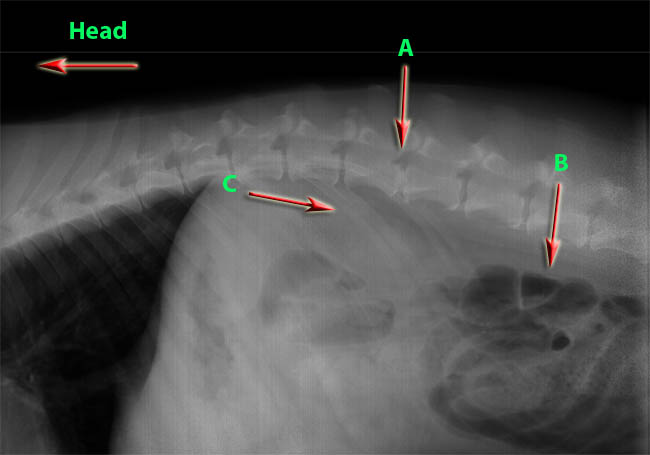

Exhibit 2:

Exhibit 2 A –

The arrow is pointing to the herniated disc.  The discs on either side of the “A” are normal healthy discs.

Exhibit 2 B –

The red arrow is pointing to the dogs intestines

Exhibit 2 C –

Both C red arrows are pointing to the ribs.

Exhibit 2 Head –

The arrow is pointing to the direction of the Gabe’s head. The opposite direction is to the Gabe’s tail.